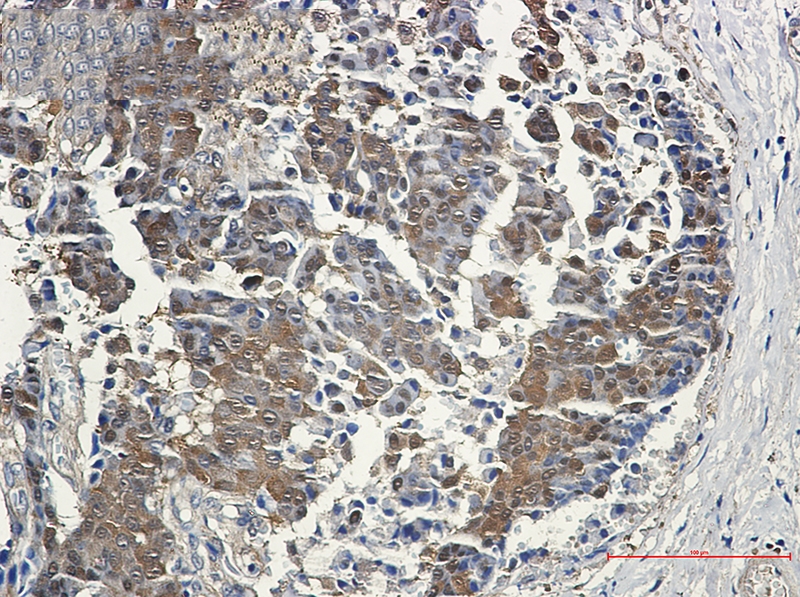

Immunohistochemistry of eIF4EBP1 in paraffin-embedded Human breast cancer tissue using eIF4EBP1 Rabbit mAb at dilution 1/50